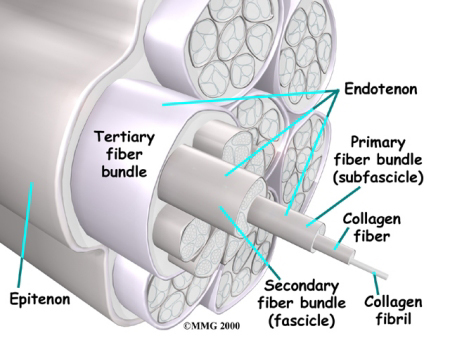

Inflammation can develop in any tendon in the body. Tendons are fibrous structures—made up of mostly collagen fibers—that connect muscle tissue to bone. Collagen is a structural protein that is the key building block of many structures in the body. Collagen helps form robust connective tissue by creating a network of collagen fibers that twist around one another in a manner that is similar to the strands of a nylon rope.

In addition to being made up primarily of collagen, the tendon is surrounded by a protective lining called a tendon sheath. The tendon sheath is filled with a lubricating fluid that helps tendons move easily against surrounding tissue. If the tendon sheath becomes inflamed, it can lead to an issue called tenosynovitis. Both the tendon and its sheath may also become inflamed at the same time.

The aging process can also lead to tendon damage. As individuals age, connective tissues within the tendon can break down or degenerate. More specifically, age-related tendon problems usually involve the degeneration of collagen. As the tissue damage progresses, pain and inflammation may alter joint mobility. Health care professionals refer to this type of issue as tendonosis.

Some researchers believe that decreased blood flow to the tendons can cause the tissue damage that leads to tendonosis. Reduced blood flow prevents sufficient amounts of oxygen and nutrients from reaching the tendons. This causes collagen fibers to become weak and lose their rope-like structure. Damage due to degeneration is particularly common in the rotator cuff, the Achilles tendon, and tendons in the elbow.